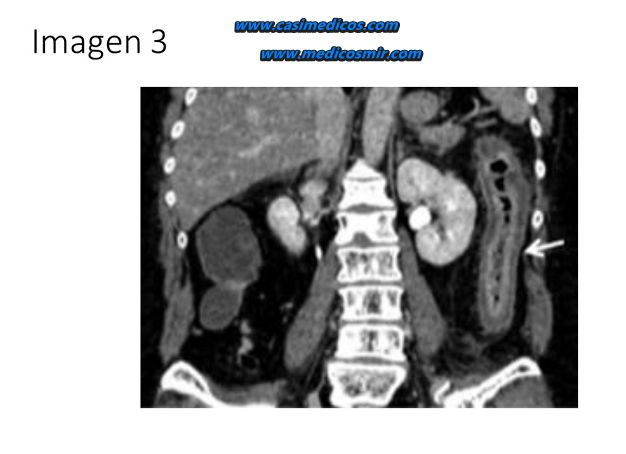

Ingresa una paciente de 83 años para tratamiento de aneurisma de aorta abdominal de 50 mm de diámetro, por crecimiento rápido en los últimos 6 meses. Entre sus antecedentes destaca: hipertensión arterial, dislipemia, portadora de marcapasos por bloqueo auriculo-ventricular completo como antecedentes. Veinticuatro horas tras la cirugía la paciente presenta distensión, dolor abdominal y rectorragias, acompañado de leucocitosis 32.100/µl, con el 95% de neutrófilos y 278 de LDH como únicas alteraciones analíticas, por lo que se realiza un angio-tomografía computarizada, con la siguiente imagen (IMAGEN 3). ¿Cuál es el diagnóstico más probable?

Comentario: TC abdominal en que se observa engrosamiento parietal del colon descendente sugestivo de colitis isquémica.